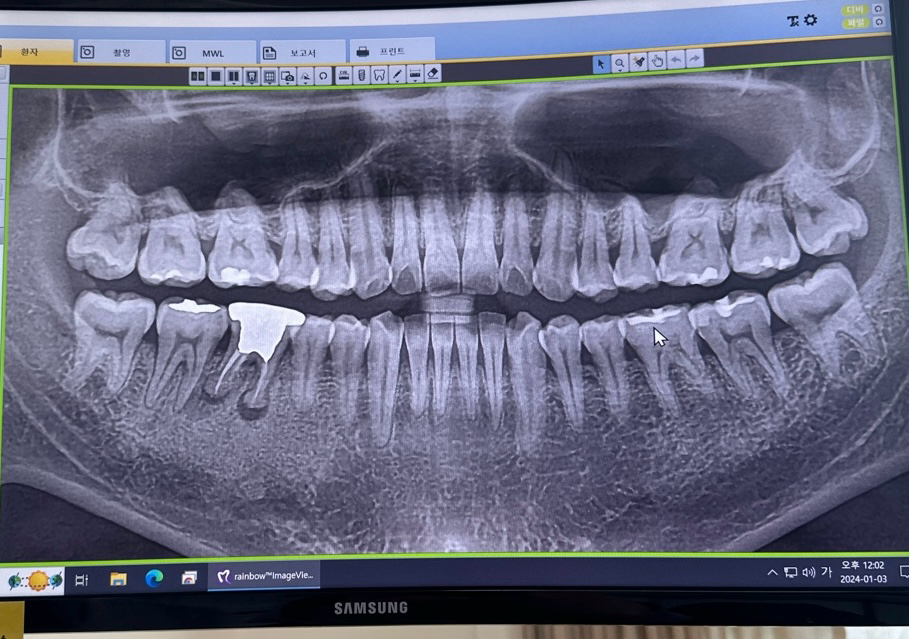

치과에서 무조건 뽑고 임플란트해야된다는데요

사진의 왼쪽아래부분에 뿌리가 둥그런 곤봉모양인경우에

금으로 한 20년전쯤 때운건데 거기에 구멍이 나고

아래쪽으론 염증이나서 치료는 안되고 무조건 뽑고 임플란트해야한다고합니다 맞을까요..?

• 1번 째 사진